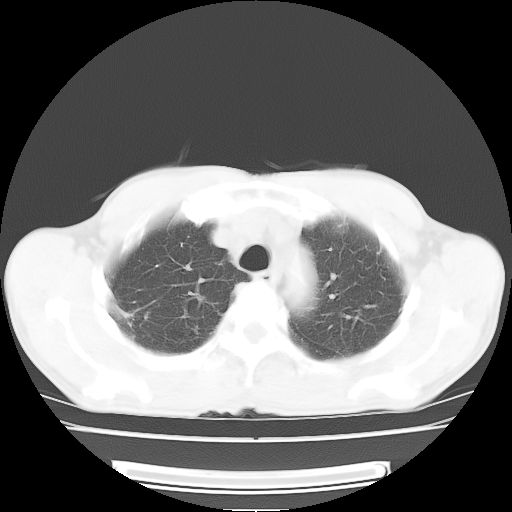

标题: CT25795:感冒后反复咳嗽两月余,痰中带血半月余。X诊断“肺 [打印本页]

标题: CT25795:感冒后反复咳嗽两月余,痰中带血半月余。X诊断“肺

1.双肺肺梗塞(理由:病灶呈三角形,与胸膜相连且局部胸膜肥厚,左心室增大)伴肺感染。

肺梗塞虽然有创意,但不现实。我考虑感染性病灶。

考虑两肺感染性病变,左肺上叶舌段肿瘤性病变待排;建议抗炎治疗后复查。